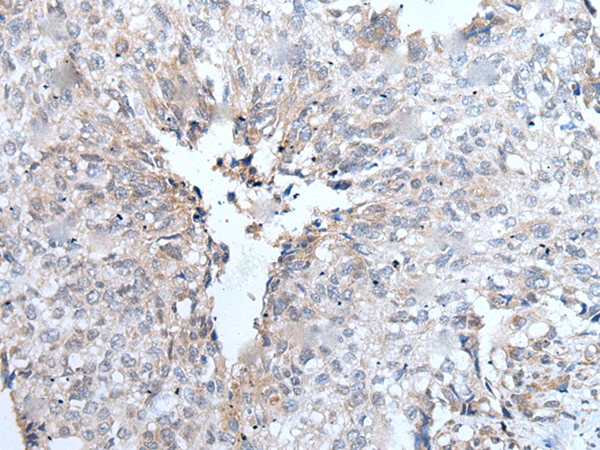

分类: 科研抗体货号: P12859别名: YB1; BP-8; CSDB; DBPB; YB-1; CBF-A; CSDA2; EFI-A; NSEP1; NSEP-1; MDR-NF1应用: IHC反应种属: Human, Mouse, Rat